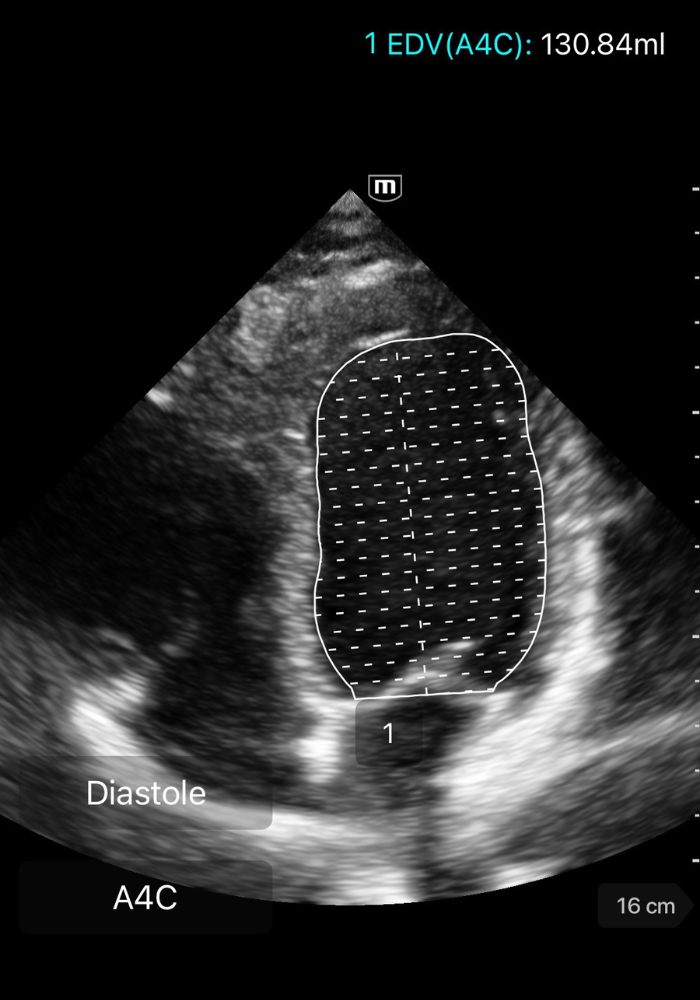

⚡️ Méthode de Simpson biplan

La méthode de Simpson biplan est la référence pour calculer la FEVG en échocardiographie transthoracique.

Elle segmente le VG en multiples coupes dont les volumes sont additionnés pour obtenir le volume télédiastolique (VTD) et le volume télésystolique (VTS).

🧭 Comment réaliser un Simpson biplan

1️⃣ Obtenir deux vues apicales orthogonales

- Apicale 4 cavités

- Apicale 2 cavités

Les deux doivent être strictement non tronqué.

2️⃣ Geler l’image en télédiastole et télésystole

-

Télédiastole = coupe où le VG est le plus large.

Télésystole = coupe où la cavité est la plus petite.

3️⃣ Tracer les contours endocardiques

Dans chaque vue (A4C puis A2C), en télédiastole et télésystole :

Placer les points de repère aux bases des feuillets mitraux.

Suivre précisément le bord endocardique jusqu’à l’apex.

Ne pas inclure les trabéculations ni les muscles papillaires dans la cavité.

➡️ La machine reconstruit ensuite un volume par empilement de coupes.

GIF ci-dessous: tracé du ventricule en diastole/systole (monoplane, démonstratif).